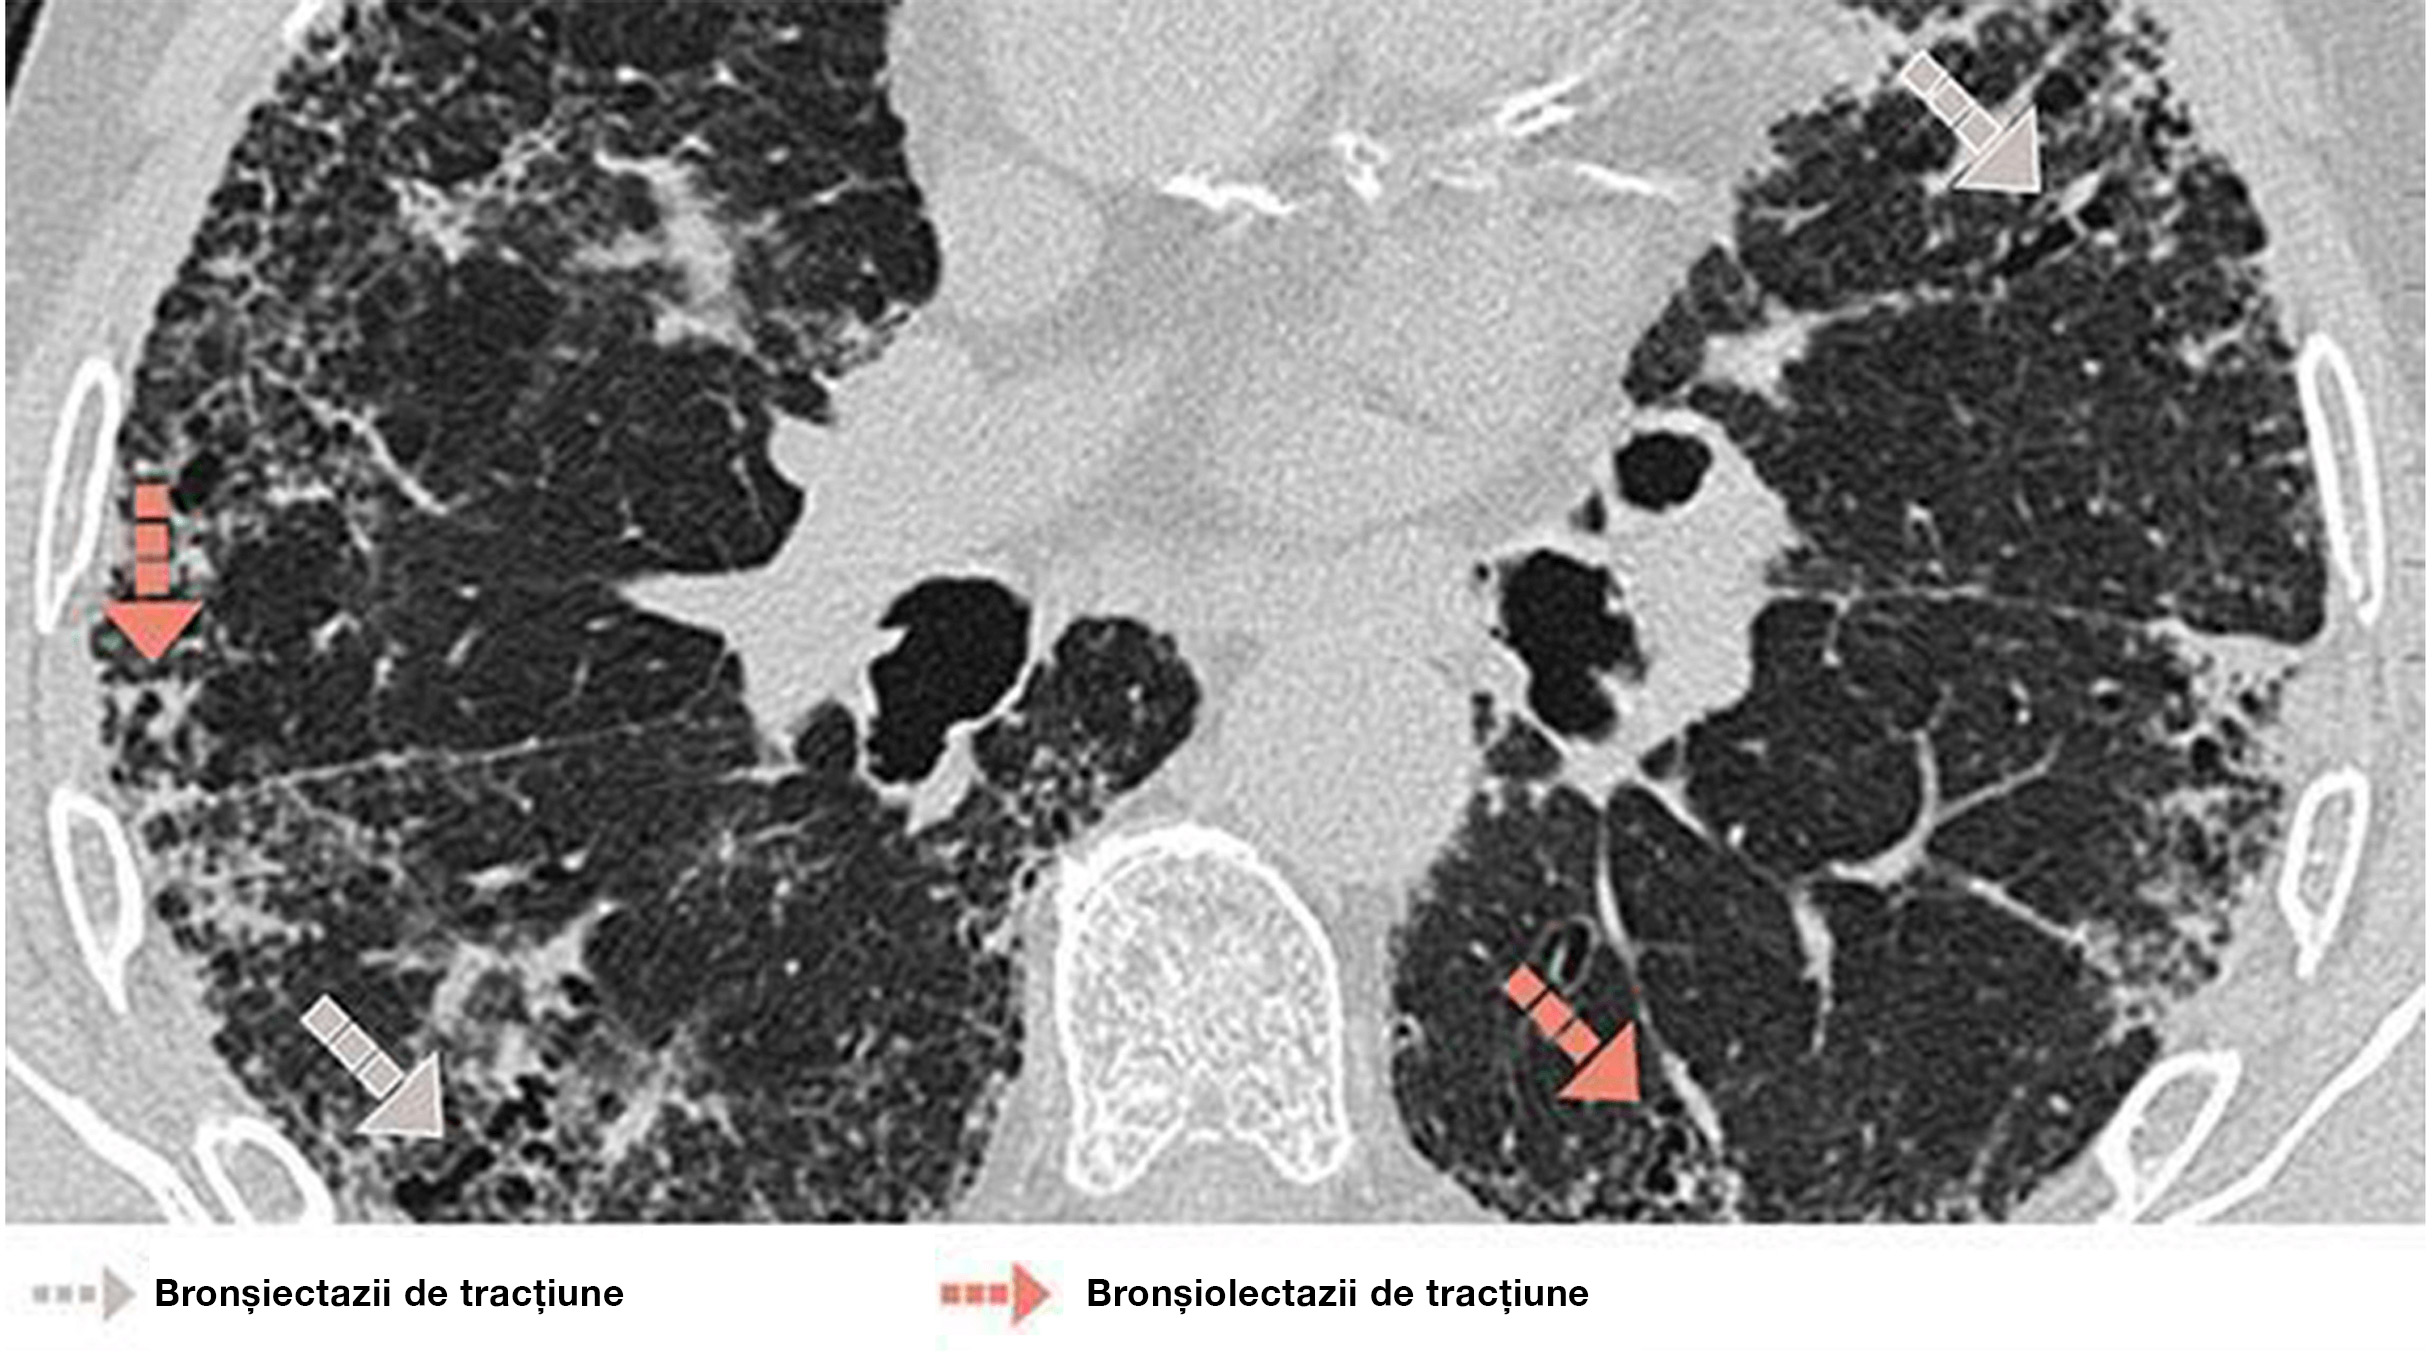

BRONȘIECTAZII DE TRACȚIUNE / BRONHIOLECTAZII

Caracteristici

• Dilatarea anormală și neregulată a bronhiilor/bronhiolelor din cauza inflamației tractului respirator (uneori reversibilă) sau a fibrozei pulmonare

• La scanarea HRCT, apare ca o creștere a calibrului tractului respirator distal (fără reducerea diametrului periferic, vizibilă pulmonar subpleural la cel puțin 20 mm de pleură)

• La scanare, se prezintă ca spații de aer tubulare sau chistice în funcție de orientarea bronhiilor în secțiune transversală.

• Diferențierea între bronșiectaziile de tracțiune și aspectul de fagure de miere este uneori dificilă pe secțiunile transversale axiale. Secțiunile transversale sagitale sau coronale și minIP sunt cele uzuale.

Diagnosticul orientativ

• Bronșiectaziile de tracțiune sunt asociate cu semne de fibroză

BRONHIOLECTAZIE

Bărbat de 72 de ani cu UIP. HRCT evidențiază reticulații difuze și bronșiolectaze și bronșiectazii de tracțiune.